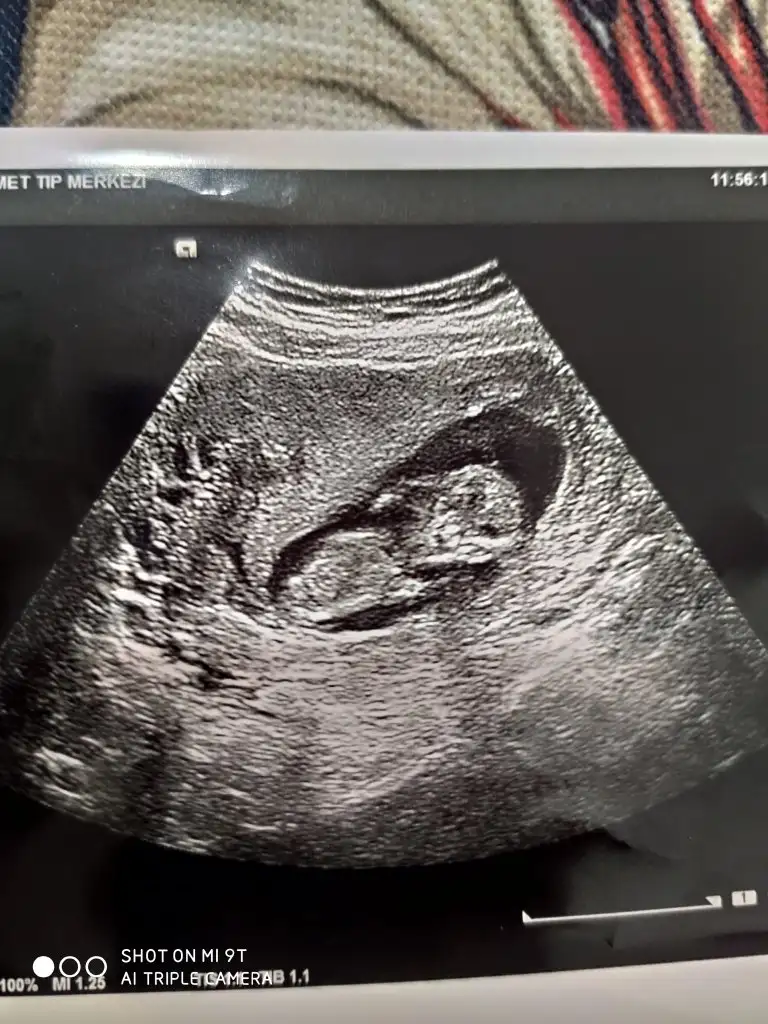

Erkek olma ihtimali çok yüksek bence

Teşekkür ederimm. Doktor bugün kız gibi duruyor dedi ama net bir şey söylemedi bacağıyla kapattı. Ben de erkek olduğunu düşünüyorum baştan beri öyle hissediyorumErkek olma ihtimali çok yüksek bence

Kız görünüyor

Haydi bakalım canim, herkes kiz dedi. Sen erkek. Son durumu paylaşacağım.Erkek gibi sanki